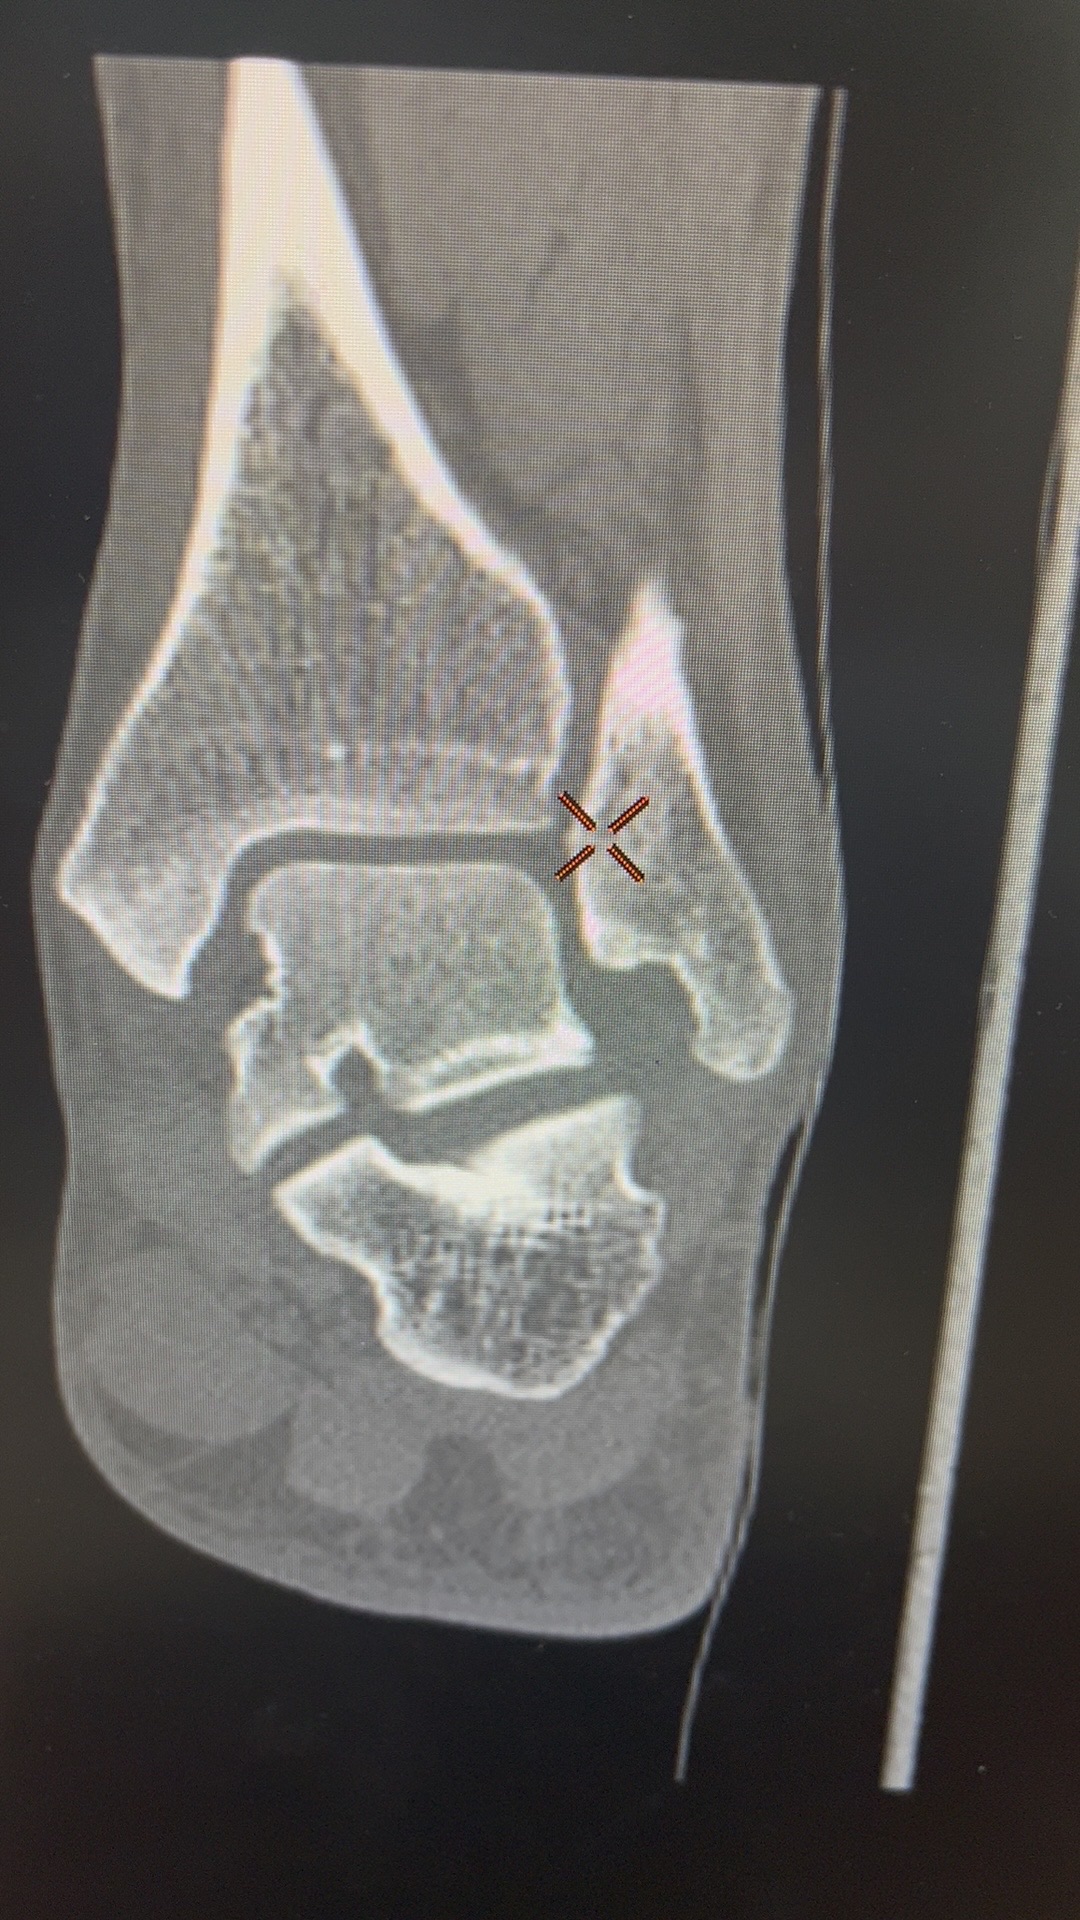

辅助检查:X线及CT示:左侧外踝骨折。

临床诊断:左侧外踝骨折